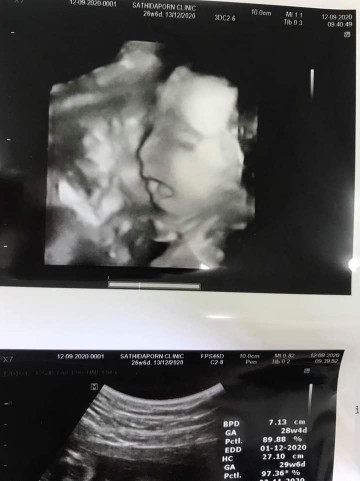

กำหนด ธ.ค. ค่ะ

13ธันวาครับ🤣